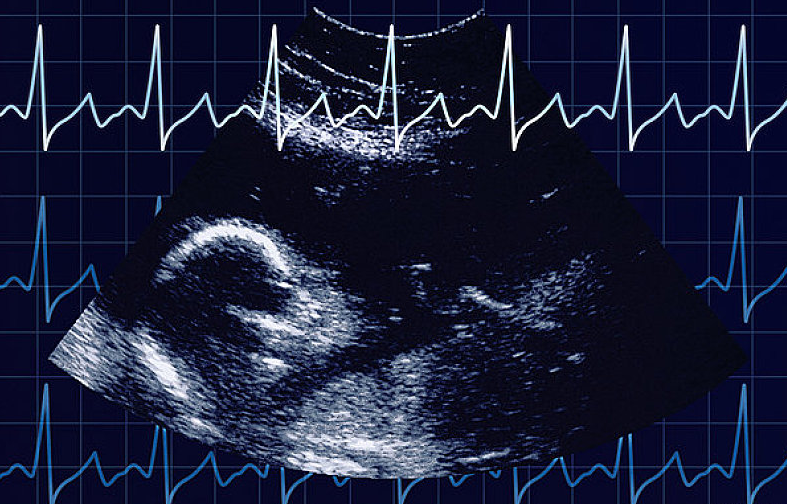

通過(guò)胎心監(jiān)護(hù)能了解到胎兒在子宮內(nèi)的情況,因此,孕媽們應(yīng)按時(shí)產(chǎn)檢,從孕32周(患有妊娠高血壓等疾病的孕媽從孕28周)開(kāi)始就要進(jìn)行胎心監(jiān)護(hù)。

當(dāng)各種原因引起胎兒缺氧時(shí),胎心很敏感地會(huì)出現(xiàn)變化。胎兒正常的胎心率為110~160次/分,正常的胎兒心率隨子宮內(nèi)環(huán)境的不同,時(shí)刻發(fā)生著變化,胎心率的變化是中樞神經(jīng)系統(tǒng)正常調(diào)節(jié)機(jī)能的表現(xiàn),也是胎兒在子宮內(nèi)狀態(tài)良好的表現(xiàn)。若胎心率分或>160次/分,持續(xù)10分鐘以上,稱(chēng)為胎心過(guò)緩或胎心過(guò)速。